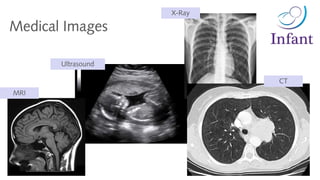

Medical Images

X-Ray

CT

Ultrasound

MRI